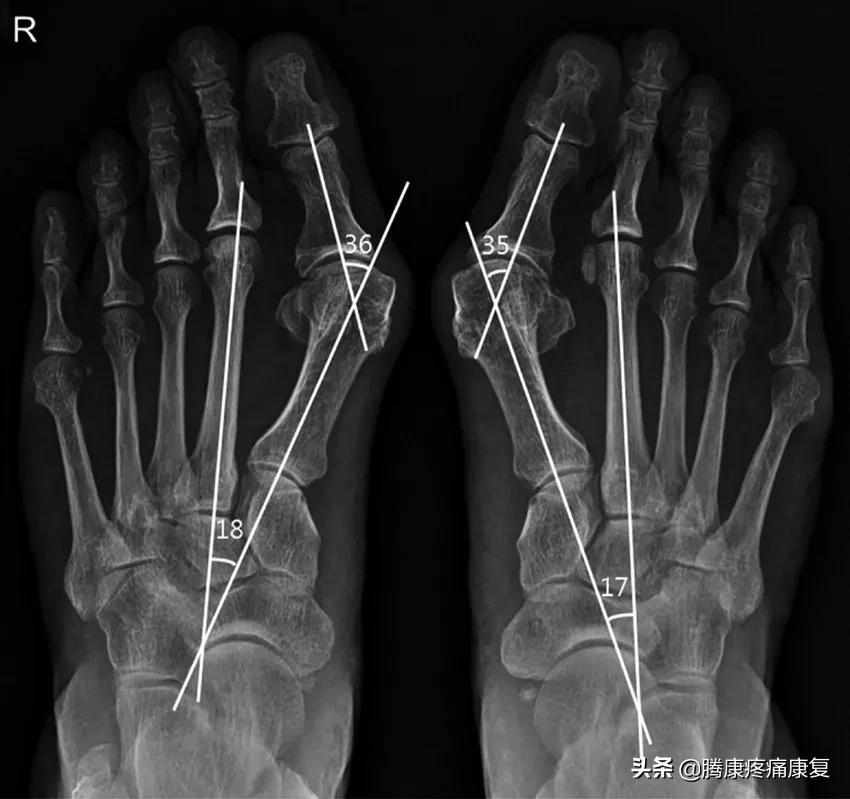

虽然我们从外观上就能分辨出来,但是医生还是需要通过X光等其他检查来测量外翻的严重程度,MRI还能辅助检测足部的软组织损伤、残留的软组织和骨骼的损伤。

根据测量的外翻角度,拇外翻被分成下面几个等级:

• 正常:10°以内的外翻仍被视为正常。

• 轻度:15~20°的外翻被视为轻度外翻。

• 中度:20~40°的外翻被视为中度外翻。

• 重度:40°以上的外翻是严重外翻畸形。